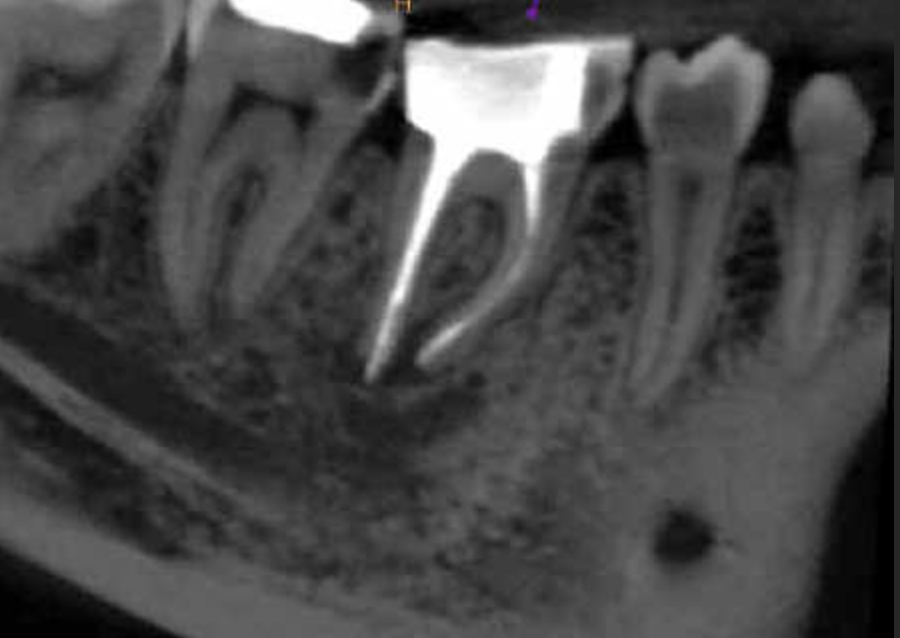

Molar superior anatomía compleja